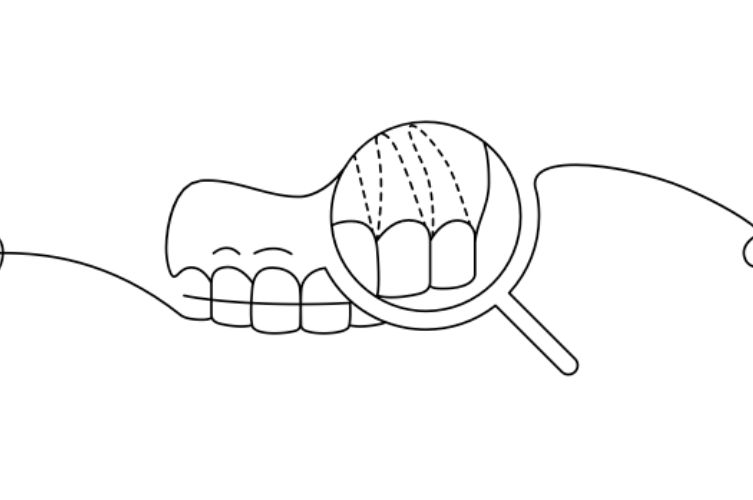

Serrer ou grincer des dents, de jour comme de nuit, provoque une usure progressive des surfaces

dentaires. La gravité du bruxisme — déterminée par la fréquence des épisodes et la force exercée —

peut entraîner une abrasion plus ou moins importante : les dents se raccourcissent, l’émail s’amincit et,

dans les cas sévères, même la dentine peut être endommagée.

• Usure dentaire (aplatissement ou abrasion des surfaces)

• Hypersensibilité dentaire

• Petites fissures ou éclats de l’émail

• Protéger les dents

Lorsque nous serrons ou grinçons des dents, l’émail s’use et, dans les cas plus sévères, des fissures ou micro-fractures peuvent apparaître.

La gouttière occlusale agit comme un coussin entre les deux arcades, prévenant ces dommages et préservant la structure dentaire.